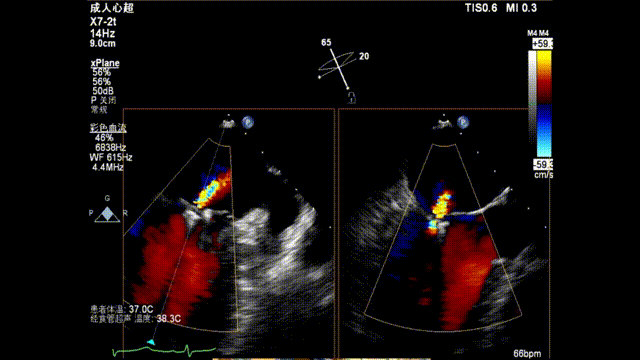

术前TEE显示重度功能性二尖瓣反流,反流位于A2/P2;